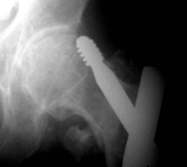

Typische pertrochantäre Femurfraktur